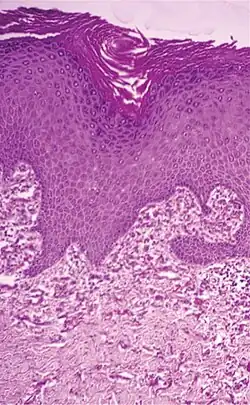

Subcutaneous tissue from a young rabbit. Highly magnified. (Elastic fibers labeled at right)